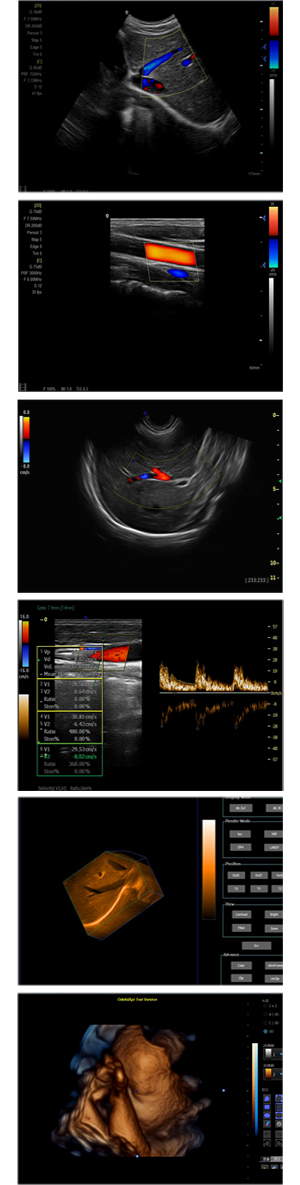

XF-7700型,秉承先鋒彩超技術(shù)之精華,擁有高雅大氣的獨特外型,為最新一代應(yīng)用型數(shù)字彩色多普勒診斷系統(tǒng),魅力與實力相融合。可廣泛適用于腹部、婦產(chǎn)科、心臟、小器官、乳腺、肌骨及外周血管等諸多方面的診查,讓您在臨床超聲診斷應(yīng)用領(lǐng)域得心應(yīng)手,綻放異彩!

突破的成像技術(shù)

● 3D/ 4D成像技術(shù)/選配

● 應(yīng)用于腹部、腎臟、泌尿系統(tǒng)、產(chǎn)科、婦科、盆腔、大動脈、肌肉組織、小器官、乳腺、心臟等

● 能量多普勒成像(PDI)

● 彩色血流量圖(CDE)

● 脈沖頻譜多普勒成像(PW)